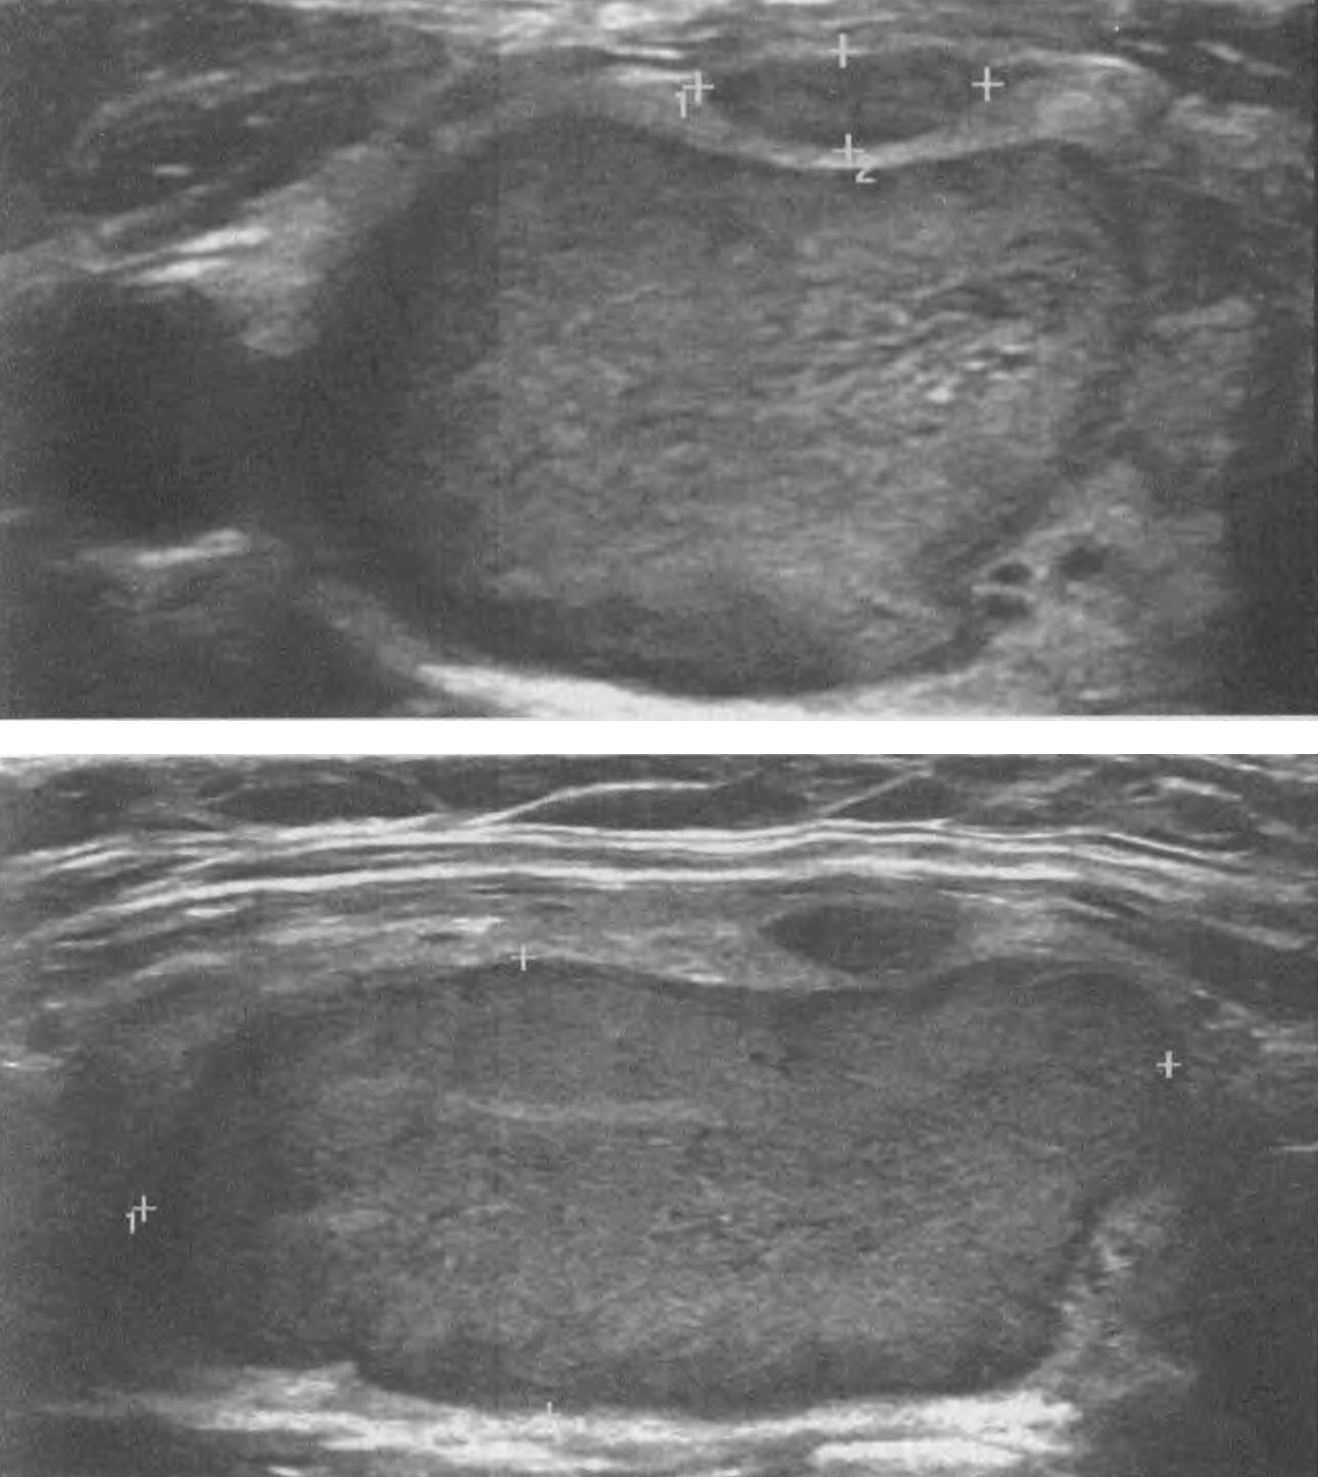

Рисунок 29. Узел 38, 2х17, 3х24,2 мм правой доли ЩЖ у пациентки 60 лет. Тканевой (2 балла); умеренно гипоэхогенный (2 балла); продольное расположение, форма повторяет долю, краниальное равномерное выпячивание связано с развитием крупного узла относительно расположенного краниально малого узла (0 баллов); равномерная граница по большей части периметра (0 баллов); характерных для рака включений нет (0 баллов). Сумма баллов 4, что соответствует 4 уровню ACR TI-RADS.

Рисунок 31. Узел 26, 1х27, 8х29,6 мм правой доли ЩЖ у пациента 46 лет. Тканевой (2 балла), преимущественно изоэхогенный (1 балл); продольное расположение, форма узла повторяет форму доли в месте расположения (0 баллов); равномерная граница по всему периметру (0 баллов); специфических для рака включений нет (0 баллов). Сумма баллов 3, что соответствует 3 уровню ACR TI-RADS. Ткань узла имеет чёткое сегментирование.